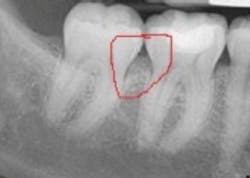

Recently, I was consulting in an office, and the insurance coordinator brought to me a situation almost identical to the one you have described. The hygienist had identified early periodontitis around some posterior teeth with 5 mm pocketing and bleeding. The patient's benefit carrier had denied coverage, stating insufficient bone loss. When I looked at the radiographs, I noticed the loss of bone definition in the molar areas, which is indicative of early periodontitis. There were not blatant vertical defects, yet the bone loss was evident. The X-ray is shown below.

Benefit providers hire people to review claims. Sometimes the reviewers are dentists that work either full or part-time reviewing claims or pre-authorizations. If the reviewer has a large caseload, claims may not get a thorough review or even a close scrutiny of documentation. In the aforementioned case, the bone loss does not appear as a clear vertical defect, but rather as a "fuzzy" area in the interproximal space. In the early stages of periodontitis, early bone loss will show up as loss of bone definition (such as loss of lamina dura).